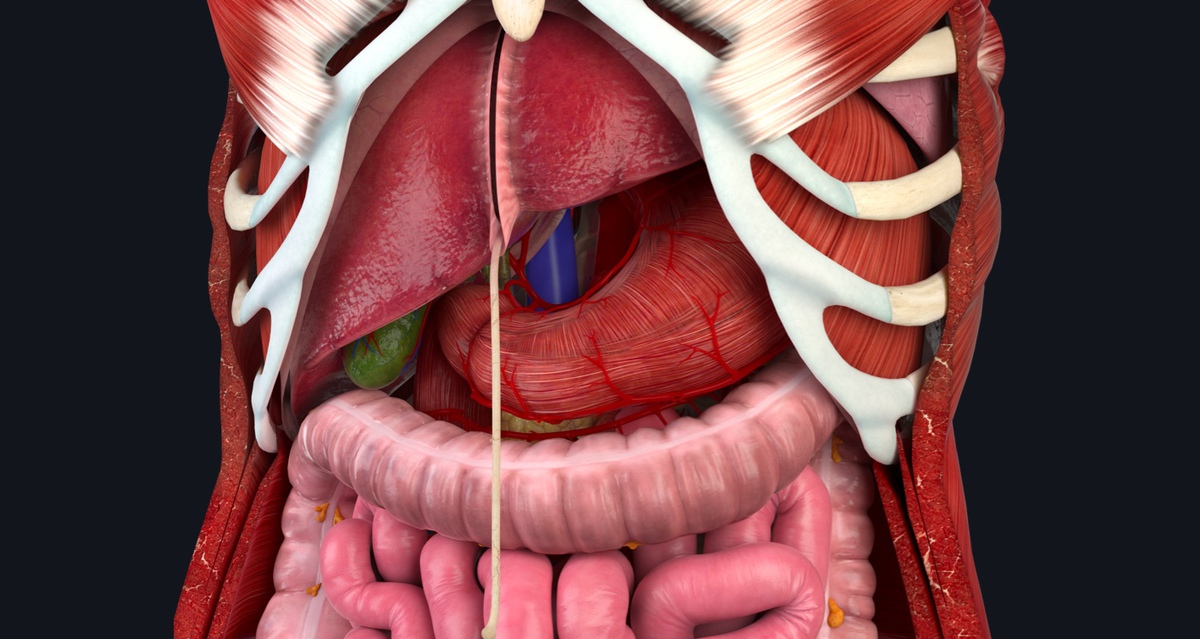

Anatomy Of The Belly

manuallistbinocular.z21.web.core.windows.netAbdominaltorsovessels

manuallistbinocular.z21.web.core.windows.netAbdominaltorsovessels